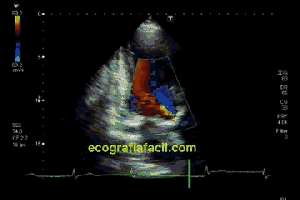

102. El Doppler.Nociones Básicas. Doppler Color.

139. Ecocardiografía. Estudio Paraesternal Eje Largo.

141. Mediciones de los planos paraesternales.